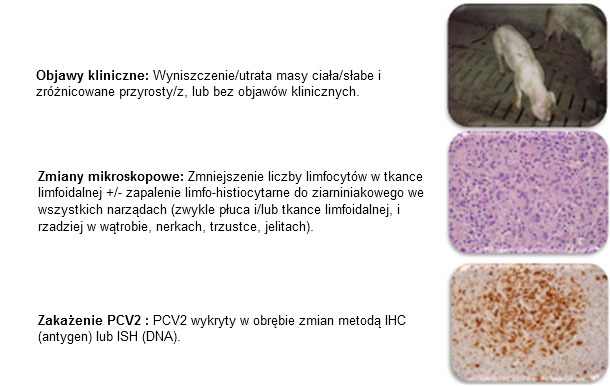

Występowanie i znaczenie zakażeń cirkowirusem typ 2 (PCV2) oraz choroby przez niego wywoływanej (PCVAD, wcześniej PMWS) uległo znacznej zmianie w ostatnich 15-20 latach. Przed rokiem 2004 PCV2 występował powszechnie w populacji świń lecz zakażenia, które wywoływał były bezobjawowe, chociaż należy pamiętać, że nie badania diagnostyczne nie były powszechnie stosowane. Opracowanie definicji choroby i kryteriów diagnostycznych rozpoznawania PMWS (czy PCVAD) przez Sordena w 2000 roku (ryc. 1) uzyskało szeroką akceptację na świecie. Sorden w swojej definicji zawarł opis kryteriów klinicznych i typowych zmian i sekcyjnych i mikroskopowych.

Ryc 1: Definicja PMWS. Sorden, Swine Health Prod 8(3):133-136, 2000

Postawienie ropoznania u świni lub grupy świń wymaga: